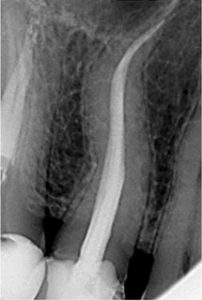

The length of the root canal is determined and the infected pulp is removed.

At the same visit, the canal where the nerve is located will be reshaped and prepared to accept a special root canal filling material.

The final step in your root canal will be the sealing of the root canal with a sterile, plastic material called gutta percha. This is done in order to prevent possible future infection.